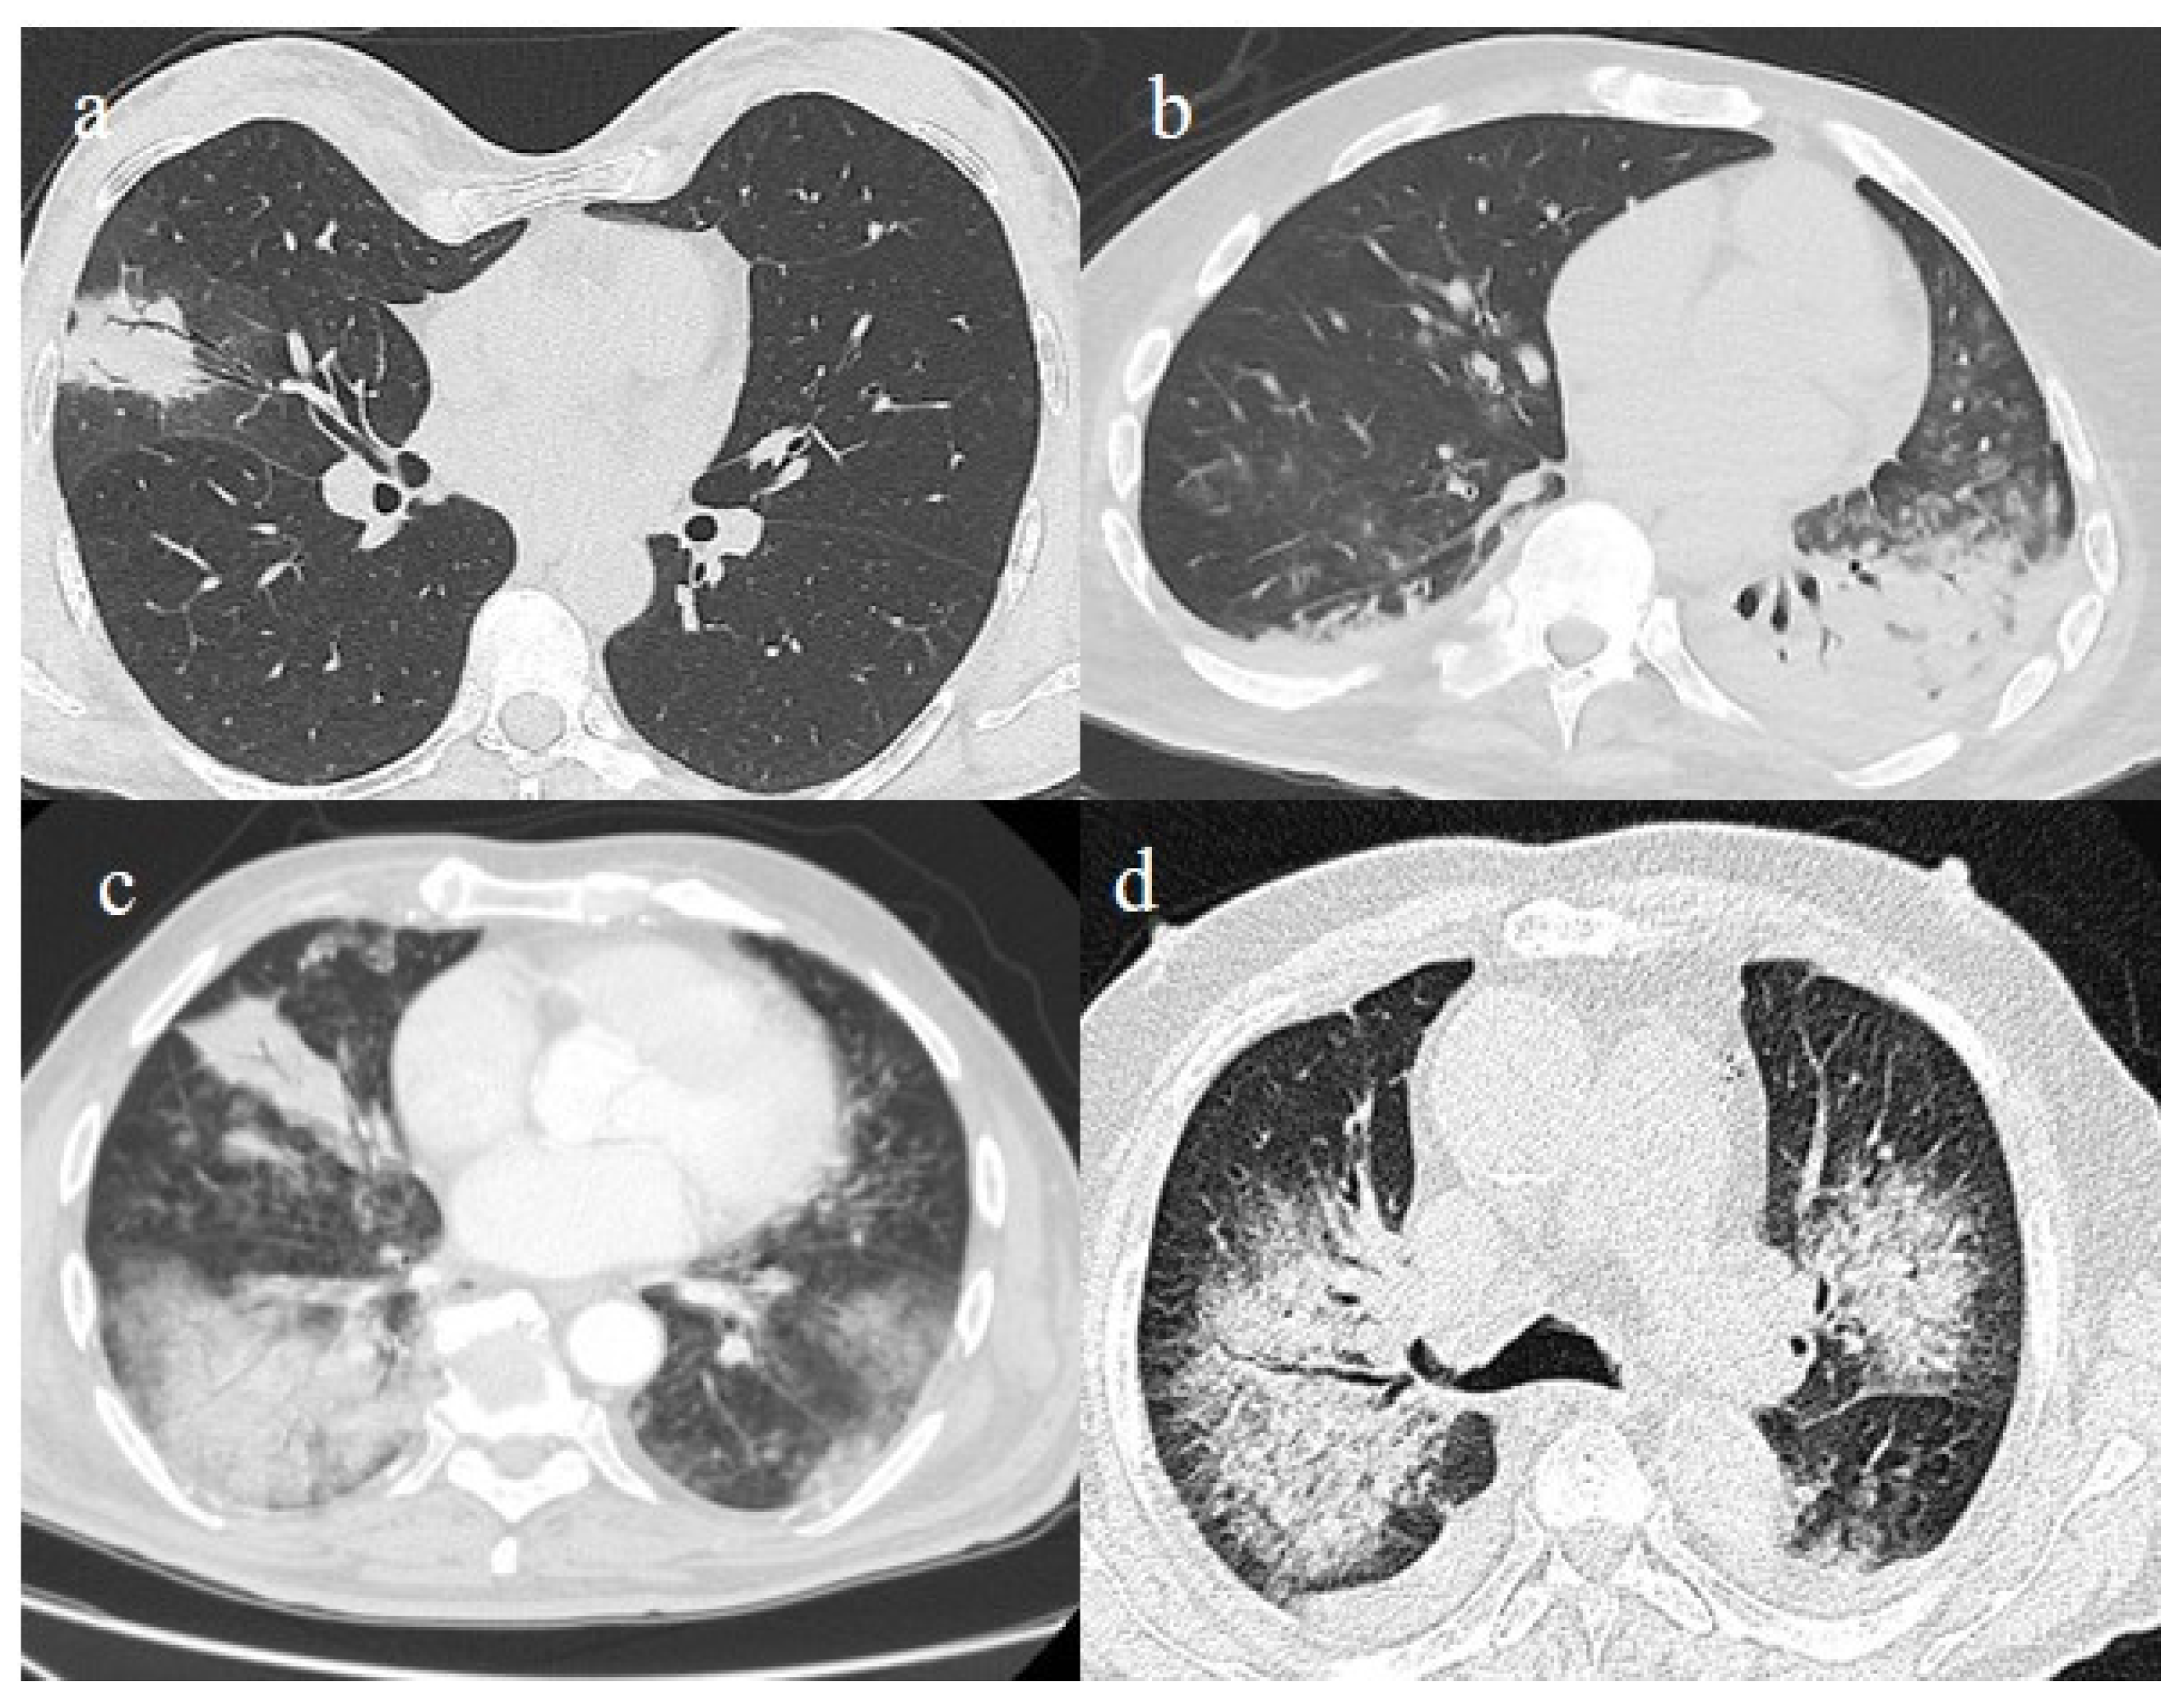

The differential diagnosis of COVID-19 pneumonia includes other infective forms of pneumonia such as bacterial pneumonia (usually lobar consolidation) and atypical pneumonia (multifocal distribution with centrilobular nodules), other viral forms of pneumonia, and cardiovascular pathologies such as pulmonary edema [62] (Figure 3 and Table 1).

Figure 3.

In this figure some differential diagnosis of COVID-19 pneumonia with atypical features are shown; in image (a), a solitary segmental bronchopneumonia is seen; image (b) shows an atypical bacteria pneumonia with consolidation areas and centrolobular nodules in a patient with immunosuppression state with positivity on BAL of Escherichia coli; image (c) illustrates an atypical pneumonia with multiple consolidations and centrolobular nodules in a patients with syncytial respiratory virus infection; image (d) shows consolidations with central hilar distribution ad bilateral pleural effusion with pulmonary edema.

It is usually possible to differentiate COVID-19 pneumonia from other viral pneumonia, such as that of influenza or syncytial and parainfluenza viruses and other coronaviruses, with a CT scan [63,64,65]. The diagnostic accuracy usually increases with the use of deep learning [66]. The resulting CT features that have been reported as the most strongly associated with COVID-19 pneumonia are the subpleural band of GGOs, where thickening of the bronchial walls and micronodules are usually more frequently associated with other viral pneumonia [63,64,65] (Figure 3c). However, some CT findings may overlap between COVID-19 pneumonia in influenza pneumonia [65]. Both COVID-19 and influenza pneumonia could show a diffused distribution; however, a lower-lobe-predominant distribution was reported to be more common in COVID-19, and an upper-lung-predominant distribution is slightly more common in influenza [65].

Figure 4.

A 41-year-old patient during the Alpha wave (November 2020). The chest CT showed diffuse interstitial thickness with GGOs in a typical distribution on the axial plane (a) and coronal plane (b) and a high score. The patient had a history of bronchial asthma with any other known comorbidities. He was treated at home with paracetamol and azithromycin. He was hospitalized and died.

Figure 5.

A 57-year-old unvaccinated patient during the Delta waves (in November 2021). On chest CT, he presented diffuse interstitial thickness with GGOs in a typical distribution in the superior and inferior lobes as visualized in image (a), in the middle and inferior lobes, in image (b) and at the lung base in image (c) and high score (CT-SS 14/25). The patient was hospitalized and died.

Figure 6.

A 51-year-old man unvaccinated patient without known comorbidities during the Delta waves (in November 2021). On CT he presented diffuse interstitial thickness with consolidation areas in a typical distribution in the superior lobes and superior and inferior lobes, on axial plane, respectively in image (a), and in image (b); diffuse interstitial thickness and consolidations on coronal plane in image (c) and high score. The patient was hospitalized and survived.